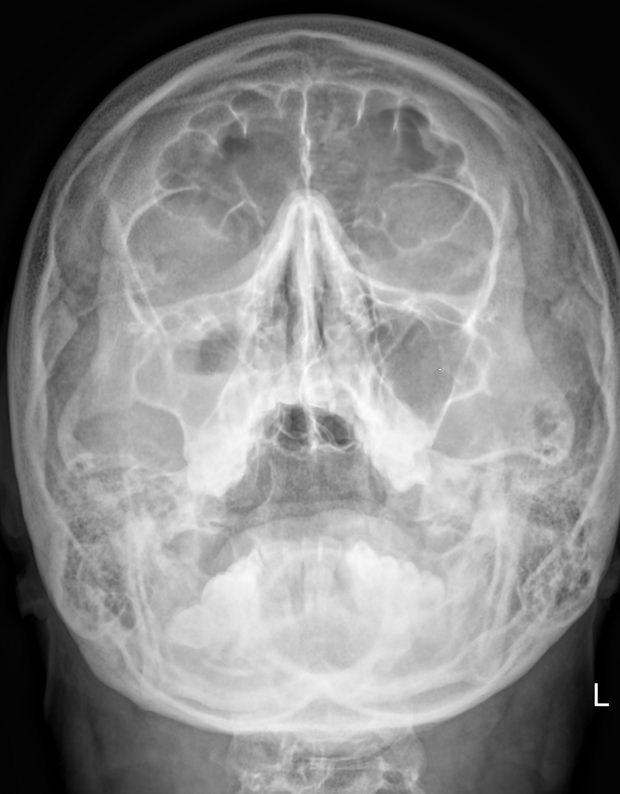

Придаточные или околоносовые пазухи носа ― это система воздухоносных полостей, располагающихся в костях черепа. Пазухи или синусы увлажняют и согревают вдыхаемый воздух, участвуют в формировании голоса, делают кости лица более легкими и смягчают силу удара при травме. К пазухам относятся:

• Гайморовы или верхнечелюстные ― расположены в верхней челюсти;

• Лобные ― в области лба над орбитами;

• Решетчатые ― позади носовых ходов  между орбитами;

• Клиновидные ― в глубине, за решетчатыми.

Что покажет рентген придаточных пазух носа

• Носовая перегородка ― прямая, искривленная, утолщенная;

• Носовые ходы ― свободны, сужены;

• Контур слизистой внутри пазух ―слизистая  обычная, утолщенная, есть рубцевания;

• Внутренние контуры ― четкие, расплывчатые;

• Наличие воздуха ― пневматизация сохранена, снижена;

• Жидкость ― в норме быть не должна, но если она есть, будет виден ее уровень;

• Новообразования;

• Инородные тела.

Правые и левые одноименные пазухи могут поражаться одновременно. Или одна быть здоровой, а другая иметь патологические изменения.